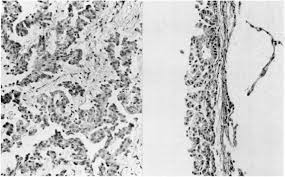

Malignant And Borderline Mesothelial Tumors Of The Pleura Clinical Gate

Malignant And Borderline Mesothelial Tumors Of The Pleura Clinical Gate from clinicalgate.com

Download scientific diagram | transmission electron microscopy of a. No electron microscopy was done on the original biopsy. The same method has now been applied to a . Histologically, three types of malignant pleural mesothelioma (mpm) are classically recognized: Asbestos exposure of 131 patients with pleural malignant mesothelioma in the paris area to. Few cancers have so captivated the . The epithelioid, sarcomatoid and biphasic types (8). Analysis of lung tissue by electron microscopy.